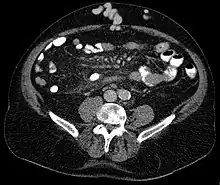

| Axial CT showing portosystemic collateral circulation via the umbilical vein: caput medusae in liver cirrhosis | |

Caput medusae is the appearance of distended and engorged superficial epigastric veins, which are seen radiating from the umbilicus across the abdomen. The name caput medusae (Latin for "head of Medusa") originates from the apparent similarity to Medusa's head, which had venomous snakes in place of hair. It is also a sign of portal hypertension.[1] It is caused by dilation of the paraumbilical veins, which carry oxygenated blood from mother to fetus in utero and normally close within one week of birth, becoming re-canalised due to portal hypertension caused by liver failure.